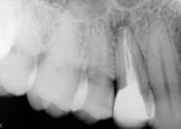

antes depois